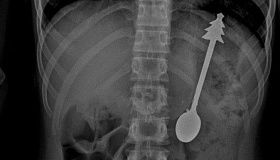

14-сантиметровую ложку проглотил ребенок в Оренбургской области

Происшествия

8 фев, 10:00

10:00